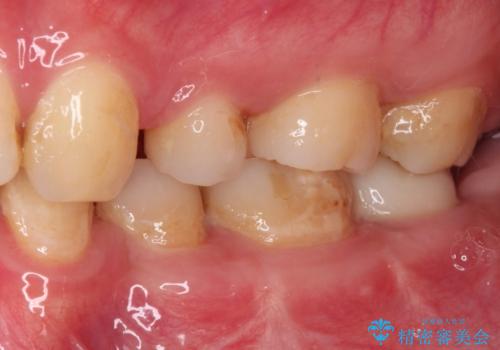

- 左下欠損部のインプラント治療と、右下の歯の痛みを気にして来院された患者様です。

左下の欠損部は、世界中で高い信頼を得ているストローマンインプラントを用いて治療を行うこととしました。

ただし、長期間欠損を放置していたことで、咬み合う上の奥歯が動いてしまっていたので、まずは上顎奥歯の部分矯正を行い、より理想的な咬み合わせを目指すこととしました。

右下の歯は、レントゲン上歯髄組織まで虫歯が及んでいるように見えましたが、痛みの症状は強くなかったため、歯髄組織の一部を断ち歯根部分の組織を保存する生活歯髄療法を第一選択に処置を進めて行くこととしました。

まず生活歯髄療法を行い、その後部分矯正やインプラント処置を行いましたが、最初の処置から1年以上経っても右下奥の処置歯の神経組織に異常は認められませんでした。

部分矯正を行ったことで、違和感のない咬み合わせを達成することができました。